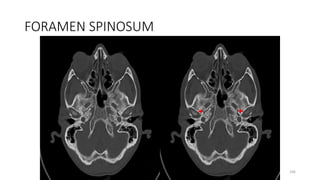

Foramen spinosum

Content

• Middle meningeal artery

• Meningeal branch of the

mandibular nerve (V3)

42

Posterior cranial fossa foramina

• Internal auditory meatus

• Jugular Foramen

• Hypoglossal canal

• Foramen magnum

43